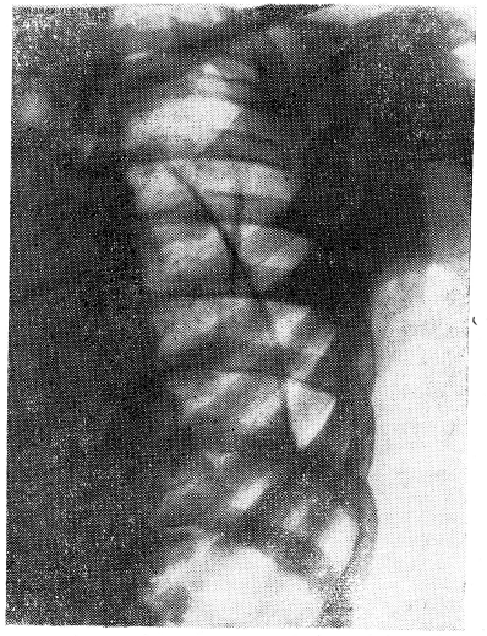

Рентгенография грудной клетки. Интенсивное гомогенное затемнение занимает почти все левое легочное поле. Проведены повторные эвакуации экссудата. После опорожнения левой плевральной полости рентгенологическое исследование выявило больших размеров остаточную полость, расположенную преимущественно в задне-боковых отделах гемиоторакса от плеврального купола и средостения до диафрагмы (рис.1)

Рис.1 Рентгенограмма левого легочного поля больной Б. после опорожнения плевральной полости.